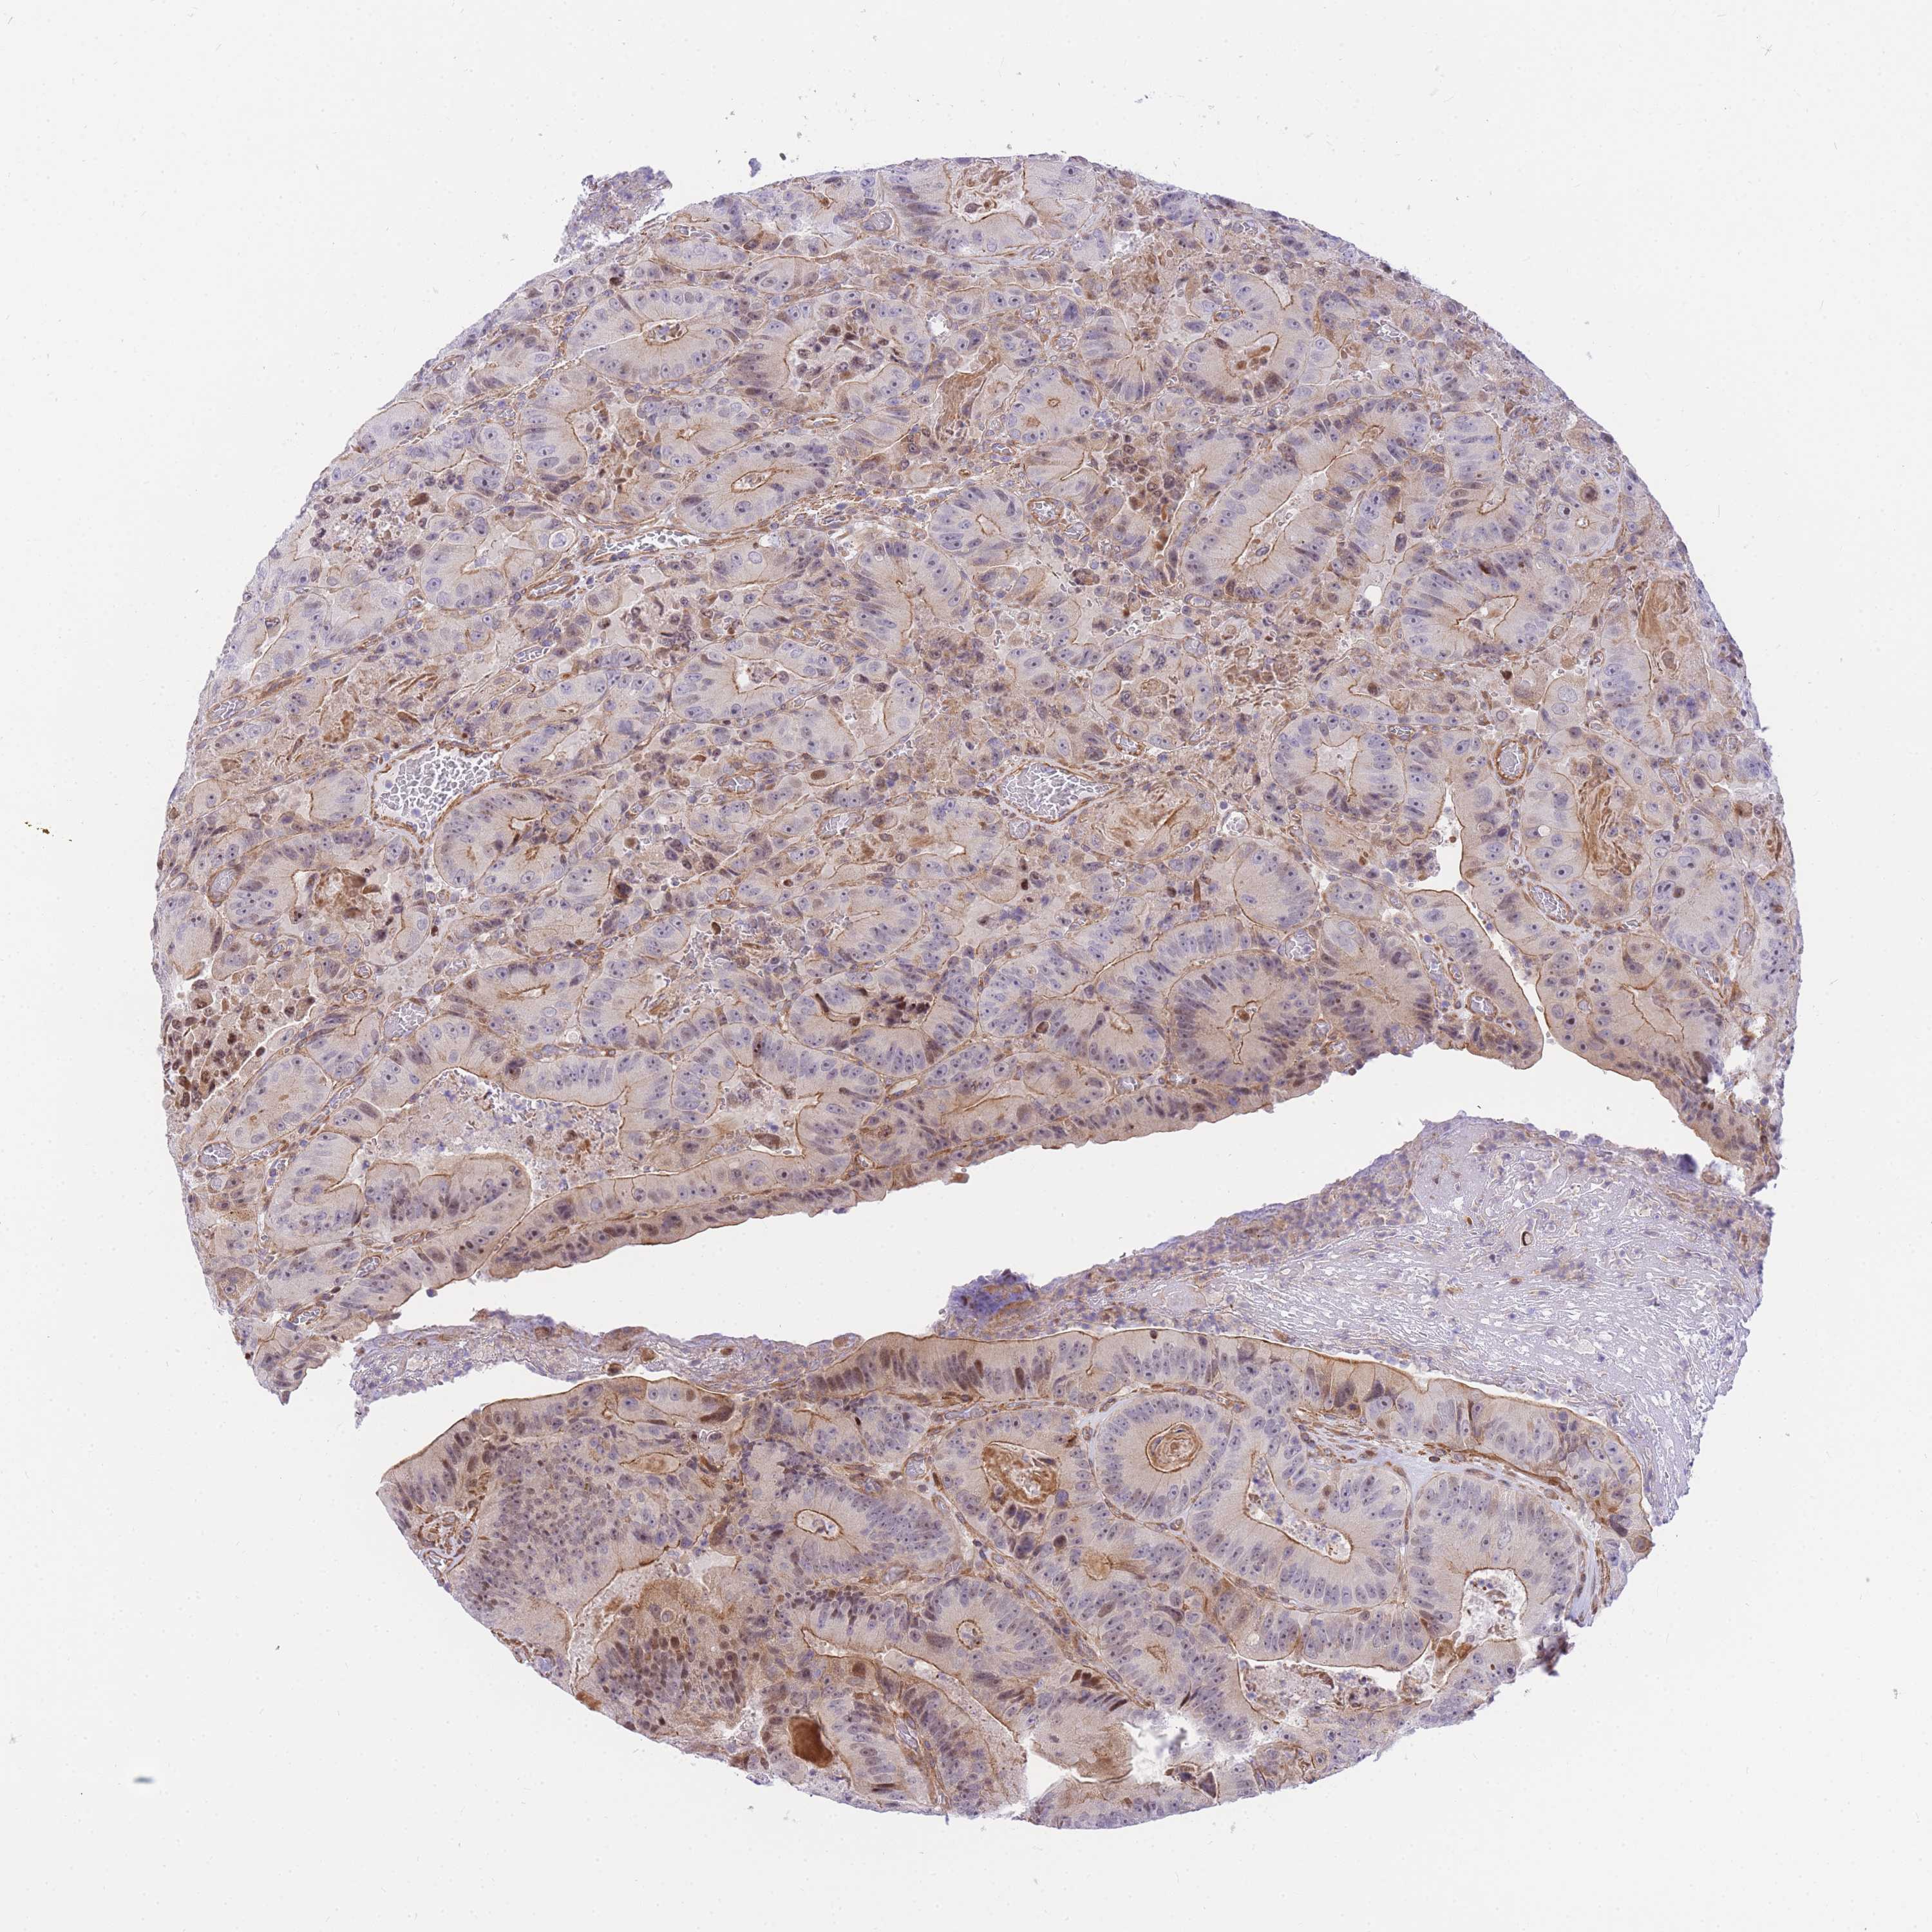

CANCER COLORECTAL CANCER Show tissue menu

Colorectal cancer

Rectum adenocarcinoma